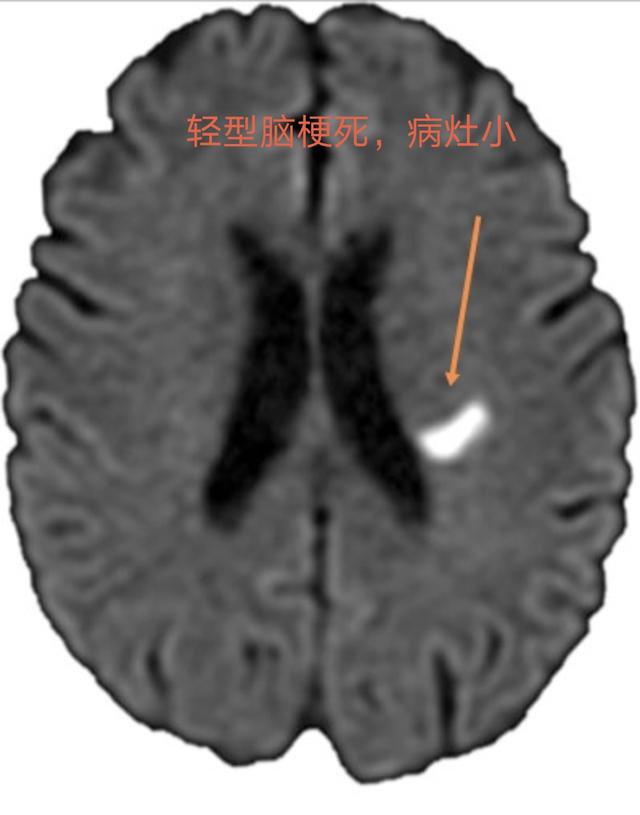

Infarctus cérébral léger ("mini-AVC")Il s'agit d'un dysfonctionnement neurologique léger et focal soudain dû à l'obstruction de petits vaisseaux sanguins.(durée ≥ 24 heures)Les manifestations les plus courantes sontlégère (symptômes, etc.)Faiblesse et engourdissement des membres, discours confus, bouche tordue, troubles de l'équilibre, non accompagnés de troubles de la conscience.La plupart des infarctus sont de petite taille ou situés dans des zones fonctionnelles non motrices, 80 % sont des infarctus lacunaires et la plupart n'entraînent pas d'incapacité significative.Mais elle provoque des lésions permanentes du tissu cérébral.

Infarctus cérébral léger : bien que l'infarctus soit petit et que les symptômes soient légers, le tissu cérébral a été endommagé et, s'il n'est pas traité à temps, il y a un certain risque que la maladie progresse et que les symptômes s'aggravent, entraînant un risque d'invalidité.

(3) Il existe une pathologie connue sous le nom d'"infarctus cérébral lacunaire" dans laquelle le patient peutAsymptomatique ou légèrement symptomatiqueLa maladie a été détectée lors d'un examen du cerveau par scanner pour d'autres affections, dont certaines étaient déjà des lésions anciennes.